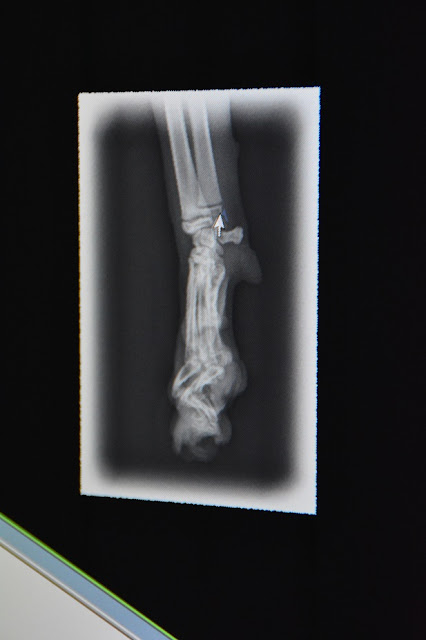

Här är då röntgenbilder på hennes tass. På den första bilden här har jag satt siffror så att jag lättare kan förklara.

1. Här ser man att leden är normal, det var inga konstigheter alls just där.

2. Denna leden har börjat dra ut sig i takt med att hon har växt och kunde i princip gå av när som helst.

3. Här ser ni hur tårna har växt ihop och det även slingrar sig lite

4. Här slutade det att växa helt, finns bara en liten stump nedanför leden.

5. Leden ovanför började också "förfalla" och troligtvis var det där klickandet kom ifrån då det skavde med den andra leden, veterinären visste inte helt säkert. Denna tån var helt sned också.

6. Handledkulan eller vad jag ska kalla det för. Den var inte som den skulle heller och hade förflyttat sig rätt så mycket. Klickandet kunde komma härifrån också, men som sagt, Elsie visste inte säkert.

Denna bilden blev inte så bra, men det är en bild från sidan av tassen. Vid siffra 1 ser ni hur kulan har förflyttat sig, det skulle vara mer jämt med benet ovanför.

Bilder utan siffror men samma som ovan